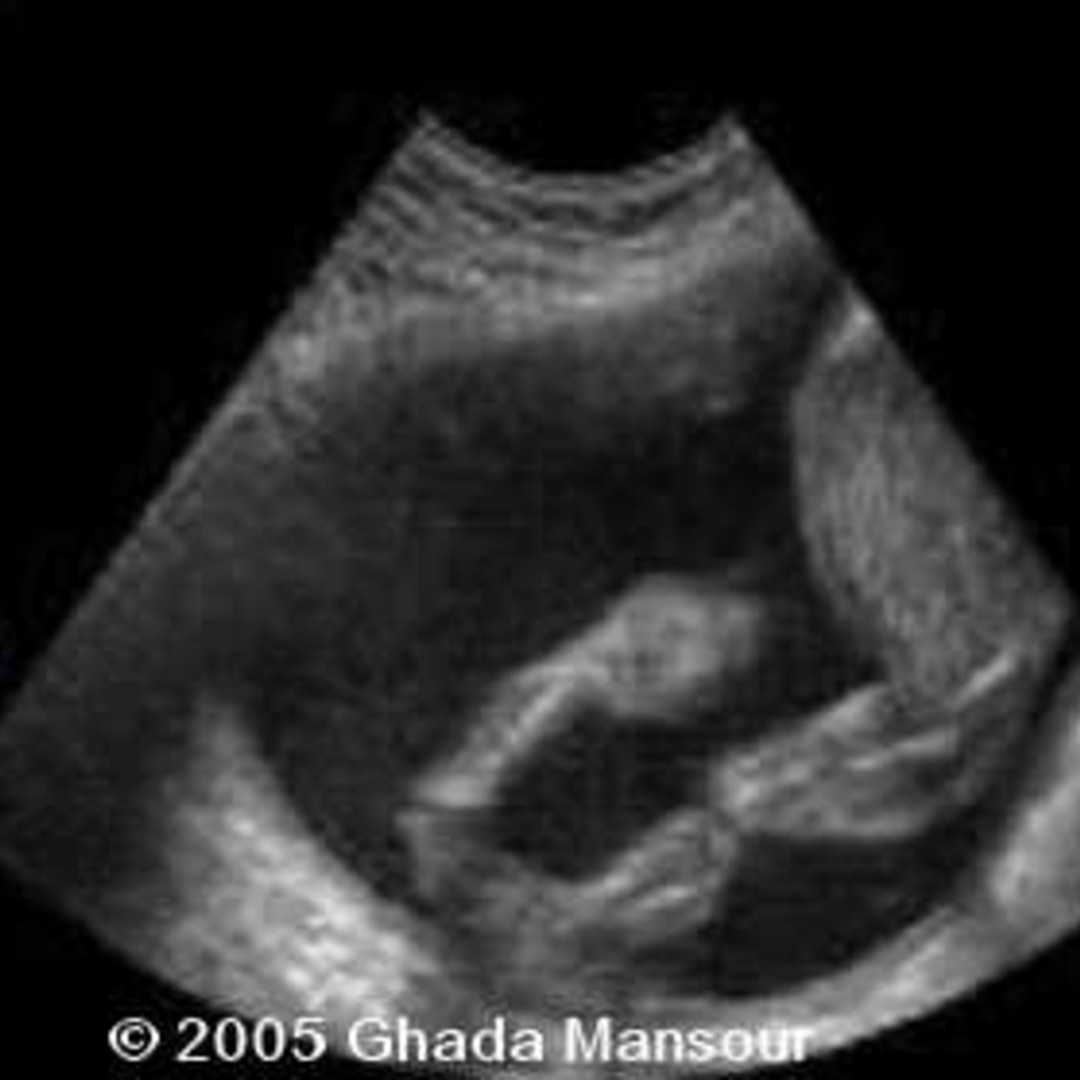

📃 Bilateral talipes equinovarus Talipes Equinovarus Procedure Web congenital talipes equinovarus (ctev), which is also known as clubfoot, is. Web congenital talipes equinovarus (ctev), also known as clubfoot, is a common congenital orthopaedic. Web this is generally followed by a small surgical procedure to lengthen the tight calf tendon at the back of the foot. Web congenital idiopathic clubfoot, also known as congenital talipes equinovarus, is the. Talipes Equinovarus Procedure.